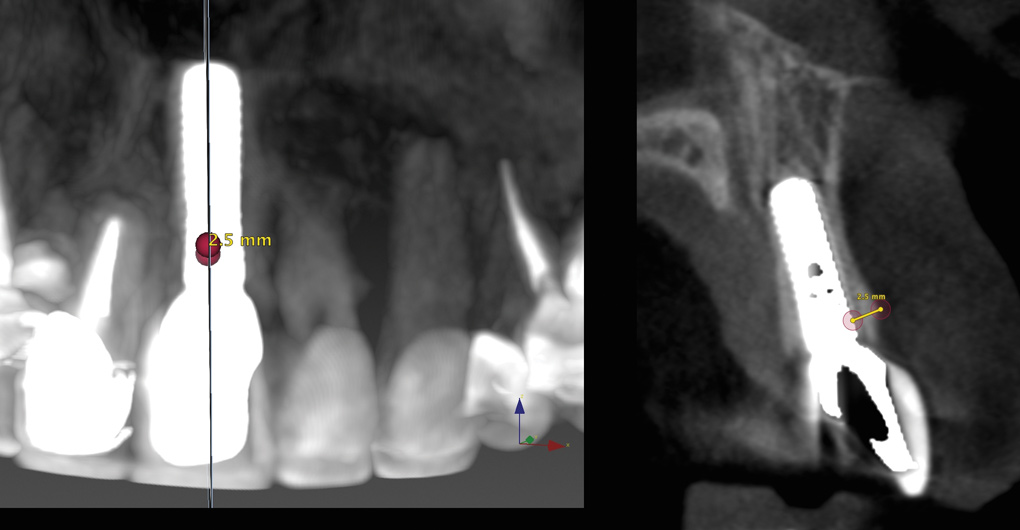

Fig 3. Pretreatment site-specific CBCT showing thick intact buccal plate and class 1 sagittal root position. Preplanning with a bone-level 4.1-mm diameter implant assured a 3-mm buccal gap upon placement and a screw-retained position.

Figure 3

Fig 4. Pretreatment site-specific CBCT showing thick intact buccal plate and class 1 sagittal root position. Preplanning with a bone-level 4.1-mm diameter implant assured a 3-mm buccal gap upon placement and a screw-retained position.

Figure 4

The patient, a healthy 45-year-old nonsmoking woman (American Society of Anesthesiologists [ASA] II), presented with a failed maxillary central incisor due to severe internal-external root resorption (Figure 1). She had a high esthetic risk profile based on 12 presenting esthetic risk factors (key No. 1), including a high lip line, high esthetic expectations, and adjacent teeth that had been restored (Figure 2).Site-specific CBCT (Carestream CS 9300, Carestream Dental, carestream.com) noted a thick intact buccal plate and a class 1 sagittal root position (Figure 3 and Figure 4). Preplanning with a bone-level 4.1-mm diameter x 14-mm long implant (Straumann Bone Level Roxolid® SLActive, Straumann, straumann.com) assured a 3-mm buccal gap upon placement and a screw-retained position (key No. 2). Prior to placement, intact buccal and palatal walls were confirmed. Figure 5 shows palatal wall placement of the implant after minimally traumatic flapless tooth extraction. An anatomically correct surgical guide template was used to assure a screw-retained position and correct vertical depth of approximately 4 mm from the mid-buccal apical extent of the guide template, which correlated to 1 mm apical of the intact buccal plate (key Nos. 3 through 5). The two-unit (8-9x cantilever) fixed provisional was recemented post-surgery. The 3-mm buccal gap was grafted tightly with a low-substitution DBBM (Bio-Oss®, Geistlich Pharma, geistlich-na.com) (key No. 6), and a pouch was created with a Buser membrane instrument (Hu-Friedy, hu-friedy.com) from line angle to line angle as a mini full-thickness flap to the mucogingival border to accept a connective tissue graft (Figure 6). The connective tissue graft, 1-mm thick x 12-mm long x 7-mm wide (Figure 7), was harvested from the palate (key No. 7).

Fig 13. Site-specific CBCT at 5 years with a measured 2.5-mm bone width facial to the implant.

Figure 13